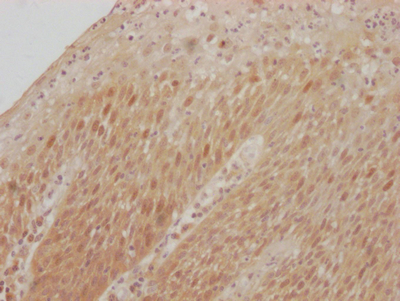

IHC image of CSB-RA961467A0HU diluted at 1:100 and staining in paraffin-embedded human tonsil tissue performed on a Leica BondTM system. After dewaxing and hydration, antigen retrieval was mediated by high pressure in a citrate buffer (pH 6.0). Section was blocked with 10% normal goat serum 30min at RT. Then primary antibody (1% BSA) was incubated at 4℃ overnight. The primary is detected by a Goat anti-rabbit IgG polymer labeled by HRP and visualized using 0.05% DAB.